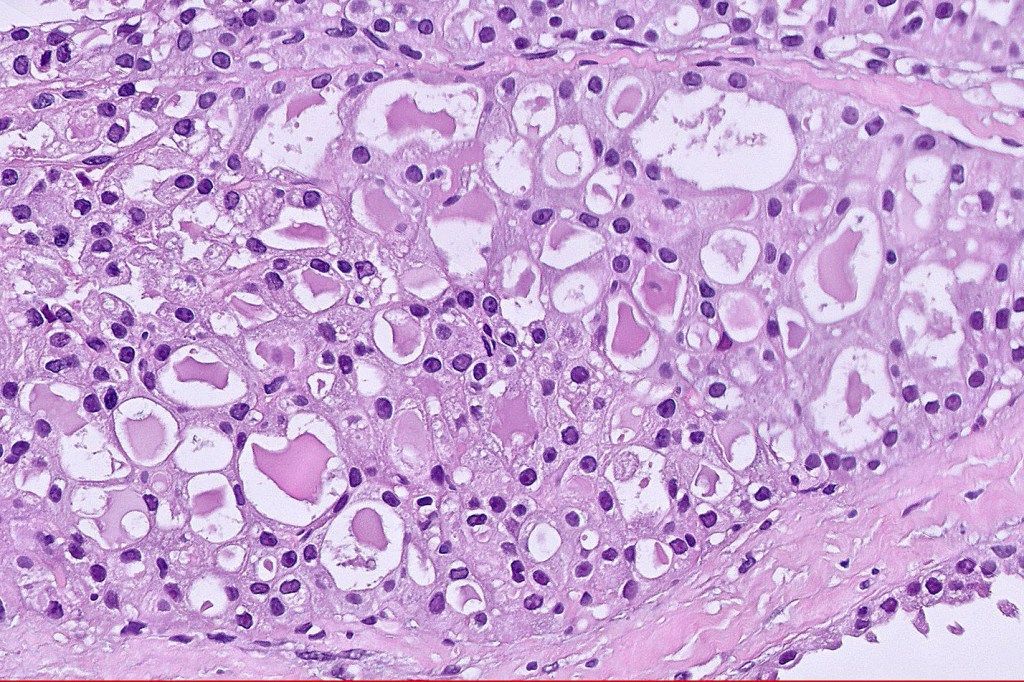

•Solid or cystic circumscribed or infiltrative dermal nodule

•Microcystic, tubular & solid patterns

•Vacuolated/granular/bubbly eosinophilic cytoplasm

•DPAS +ve luminal content

•Low grade atypia, mitoses very sparse, absence of perineural infiltration, lymphovascular invasion or necrosis